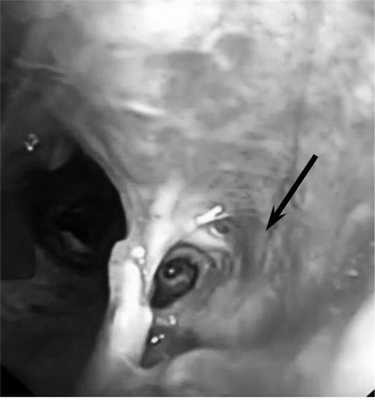

Пациент С., 28 лет, 29.07.14 был придавлен автомобилем к стене. Госпитализирован в ЦРБ г. Александрова, где при обследовании диагностирована тяжелая закрытая травма груди: множественные переломы ребер с двух сторон с разрывом легких, двусторонний пневмоторакс, правосторонний гемоторакс, подкожная эмфизема грудной клетки. Произведены правосторонняя торакотомия, ушивание разрывов верхней доли легкого, санация и дренирование правой плевральной полости, дренирование левой плевральной полости, диагностическая лапаротомия, ревизия органов брюшной полости. Через сутки (30.07.14) для дальнейшего лечения пациент переведен в НИИ СП им. Н.В. Склифосовского. При поступлении состояние больного тяжелое. Сознание - 10 баллов по шкале комы Глазго. Кожные покровы бледные, цианотичные. Искусственная вентиляция легких (ИВЛ) через оротрахеальную интубационную трубку. Грудная клетка равномерно участвовала в акте дыхания. Диагностирована двусторонняя подкожная эмфизема грудной клетки и шеи. Аускультативно дыхание жесткое, ослаблено с обеих сторон, больше справа. По дренажам из правой плевральной полости отмечено периодическое поступление воздуха. ЧСС 124 в минуту, АД 120/70 мм рт.ст. При рентгенологическом исследовании выявлена эмфизема мягких тканей грудной клетки с обеих сторон, переломы II-VII ребер справа и IV-VIII - слева, снижение прозрачности легочного поля в верхних и средних отделах правого легкого за счет контузионных изменений и кровоизлияний. При КТ-исследовании визуализированы множественные полисегментарные ушибы обоих легких с формированием гемопневматоцеле в нижней доле правого легкого, пневмомедиастинум, множественные переломы ребер и эмфизема мягких тканей передней грудной стенки. При фибробронхоскопии (ФБС) через интубационную трубку в просвете трахеобронхиального дерева, больше справа, выявлено значительное количество крови и сгустков. Выполнена санация просвета трахеи и бронхов раствором диоксидина 0,01% 60 мл. Сгустки крови удалены. В промежуточном бронхе визуализирован сгусток крови длиной 20-25 мм, занимающий 2/3 просвета бронха. По латеральной стенке бронха, не прикрытой сгустком крови, определялся дефект стенки бронха. При проведении аппарата дистальнее сгустка визуализировали среднедолевой и нижнедолевой бронхи. При ФБС, выполненной через 12 ч, в просвете бронхов определяли умеренное количество слизистого секрета с примесью крови. На 5 мм дистальнее карины по заднемедиальной стенке правого главного бронха выявлен дефект стенки 10 мм в диаметре с рваными краями и с образованием полости диаметром 10-15 мм (рис. 1). Правый верхнедолевой бронх не изменен, сегментарные бронхи проходимы. На расстоянии 10 мм от шпоры правого верхнедолевого бронха и на уровне верхнего края устья среднедолевого бронха визуализирован циркулярный разрыв стенки промежуточного бронха с диастазом краев 20-25 мм (рис. 2). Средне- и нижнедолевые бронхи правого легкого не изменены. Таким образом, локализация разрывов бронхов не позволяла исключить правостороннюю пневмонэктомию как возможный объем операции. Однако вмешательство с раздельной интубацией бронхов и выключением правого легкого на фоне массивной контузии левого легкого, выраженной легочной недостаточности и постгипоксического синдрома представлялось крайне рискованным. В связи с полным расправлением легких, отсутствием значительного сброса воздуха по дренажам из плевральной полости и нарастающей эмфиземой на фоне ИВЛ решено воздержаться от операции и выбрать консервативную тактику. Проводили комплексную интенсивную терапию: ежедневные двукратные санационные ФБС; антибиотикопрофилактика (цилапенем 4000 мг/сут в/в, метронидазол 1000 мг/сут в/в); переливание иммуноглобулина 100 мл в/в, 2 доз эритроцитной массы и 11 доз свежезамороженной плазмы крови, 100 мл/сут 10% альбумина; муколитическая, ингаляционная, противовоспалительная терапия. На 2-е сутки наложена трахеостома для продленной ИВЛ.

Рис. 1. Разрыв правого главного бронха. Дефект заднемедиальной стенки правого главного бронха 10 мм в диаметре с рваными краями и с образованием полости диаметром 10-15 мм (указано стрелкой).